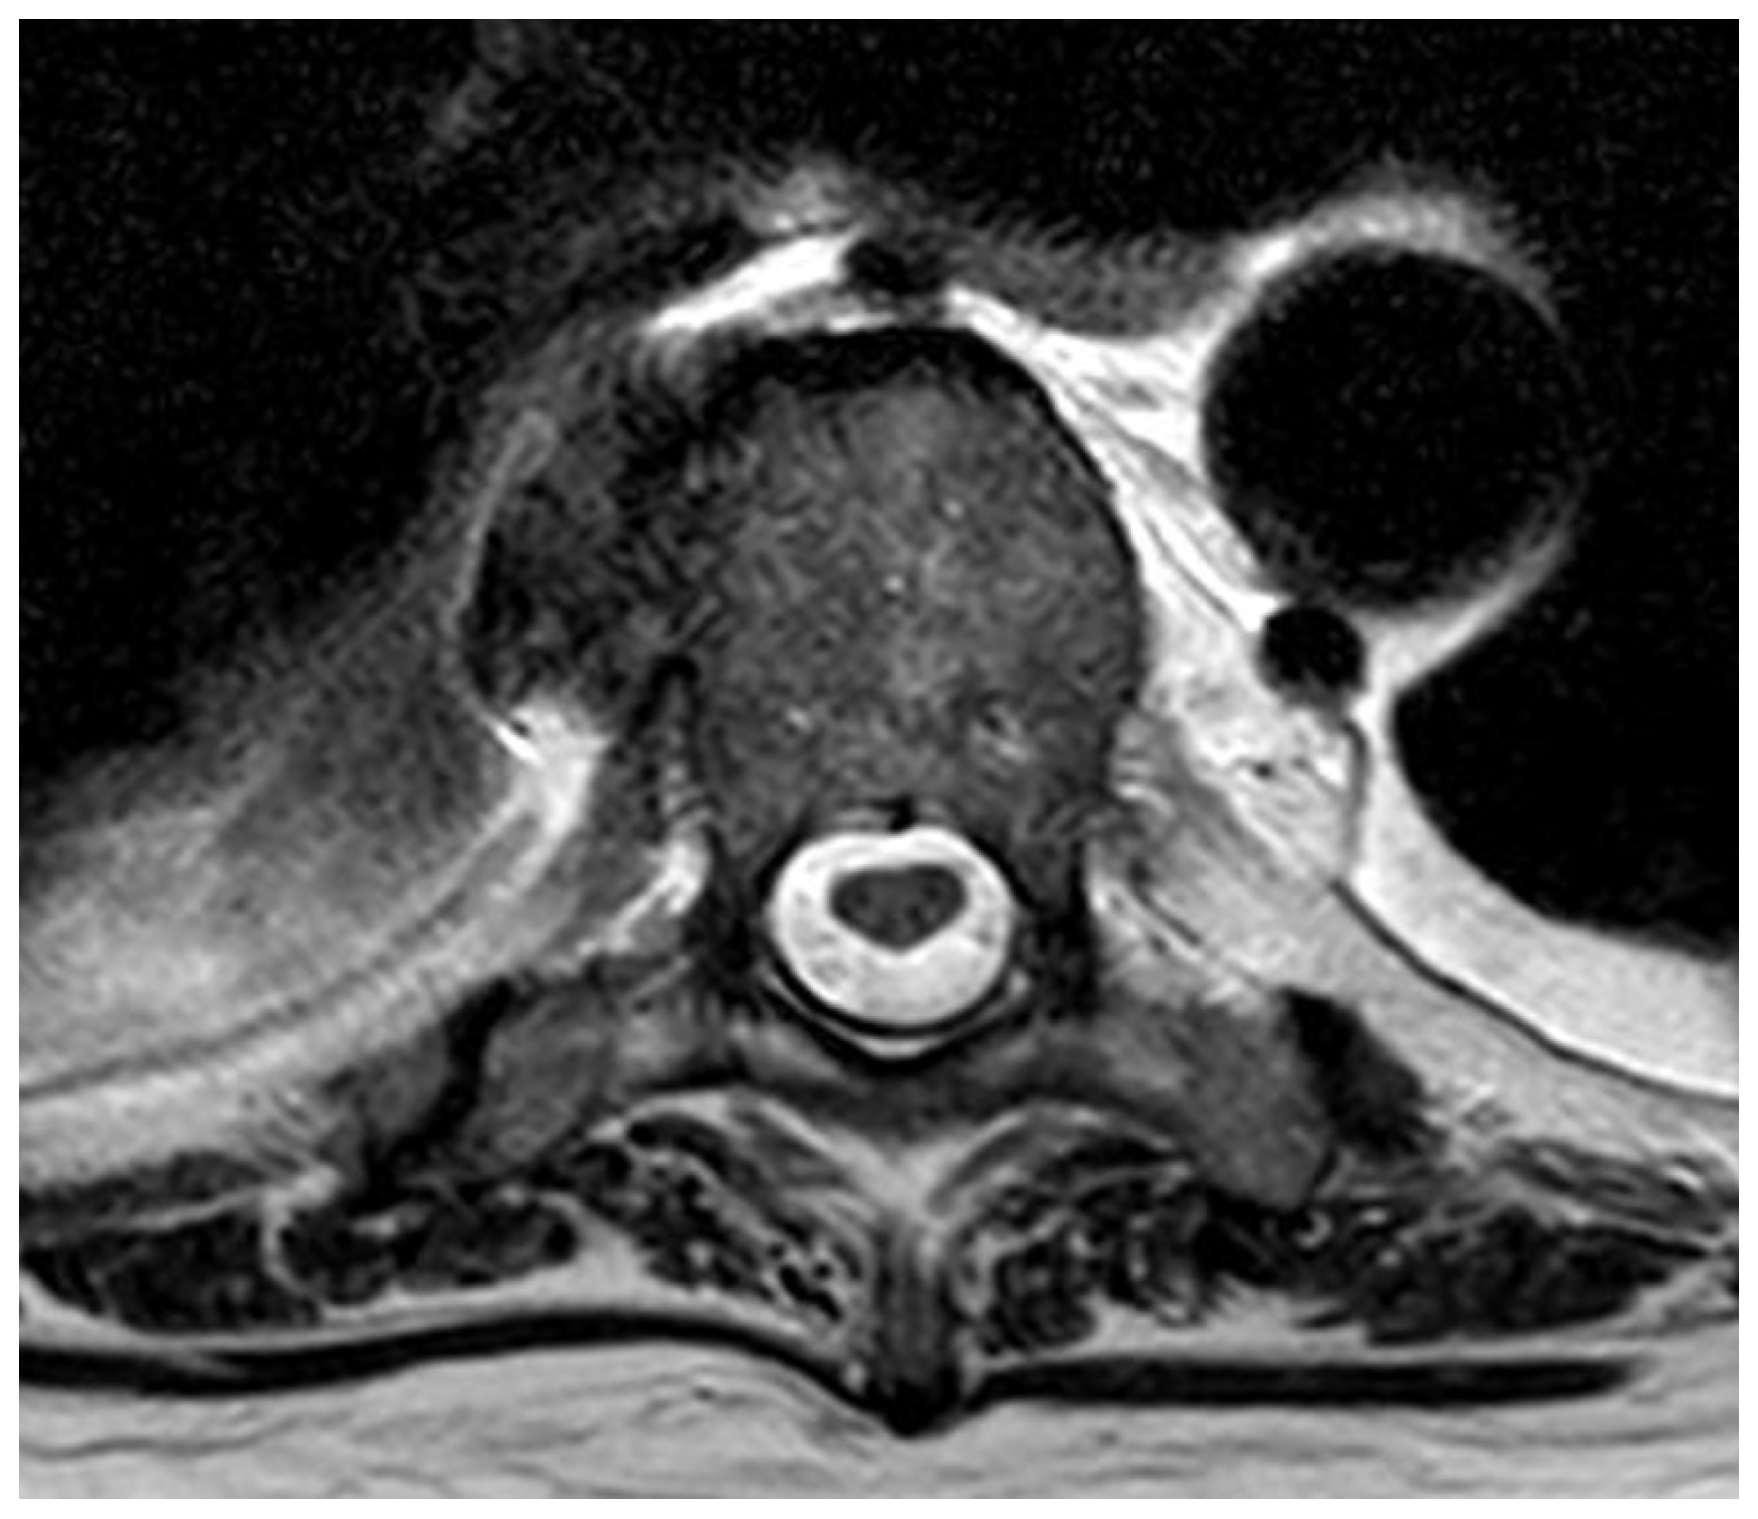

3.2.3. Case 3—Spine/Knee

- ▪ Multi-level spondylodiscitis in segments TVB 8/9, TVB 11/12, LVB (lumbal vertebra body) 2/3, and LVB 4-SVB (sacral vertebra body) 1 with inflammatory reaction and epidural abscess formation at the posterior edges of LVB 4 and LVB 5, as well as a long-distance, meningeal, inflammatory surrounding reaction at TVB 8–12 and LVB-2/SVB-1 with accompanying consecutive absolute spinal canal stenosis in the LVB 4–5 segment (Figure 4 and Figure 5)

- ▪ bilateral partially chambered psoas abscesses

- ▪ Epidural abscess at the posterior edges of LS (lumbal segment) 5 and LS6 with consecutive absolute spinal canal stenosis in the LS5/SS (sacral segment) 1 segment